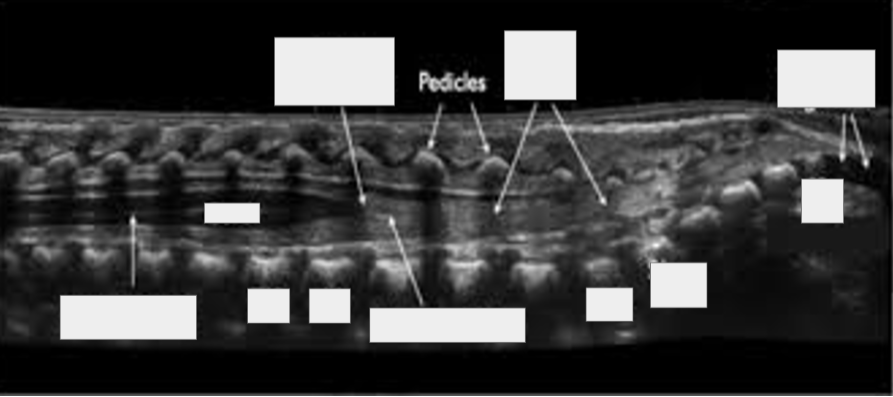

Coccygeal segments (coccyx), cord, T12, Conus medullaris, Filume terminale, L1, L5, S5, S1, Pedicles, Nerve roots (cauda equina), Central canal (central echo complex)